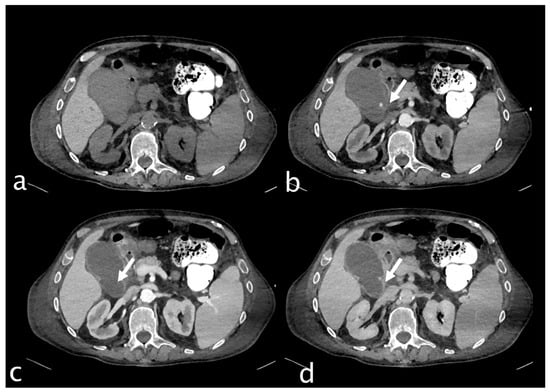

2. Imaging

3.1.3. Imaging and Diagnostic Findings